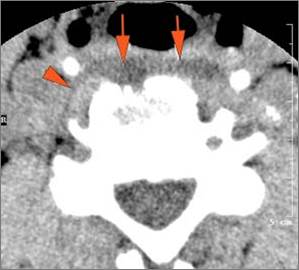

There is reactive retropharyngeal lymphadenopathy.

There is suppurative retropharyngeal lymphadenopathy.

If there is suppurative retropharyngeal adenopathy what is the maximum short axis dimension of the largest suppurative node. Measurement

There is edema/abscess within the adjacent parapharyngeal and retropharyngeal spaces.